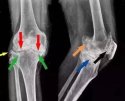

骨质增生,又称骨刺,是困扰中老年人的一种常见的骨科疾病,严重影响人们的生活和工作,得了骨增生那怎么治疗呢?